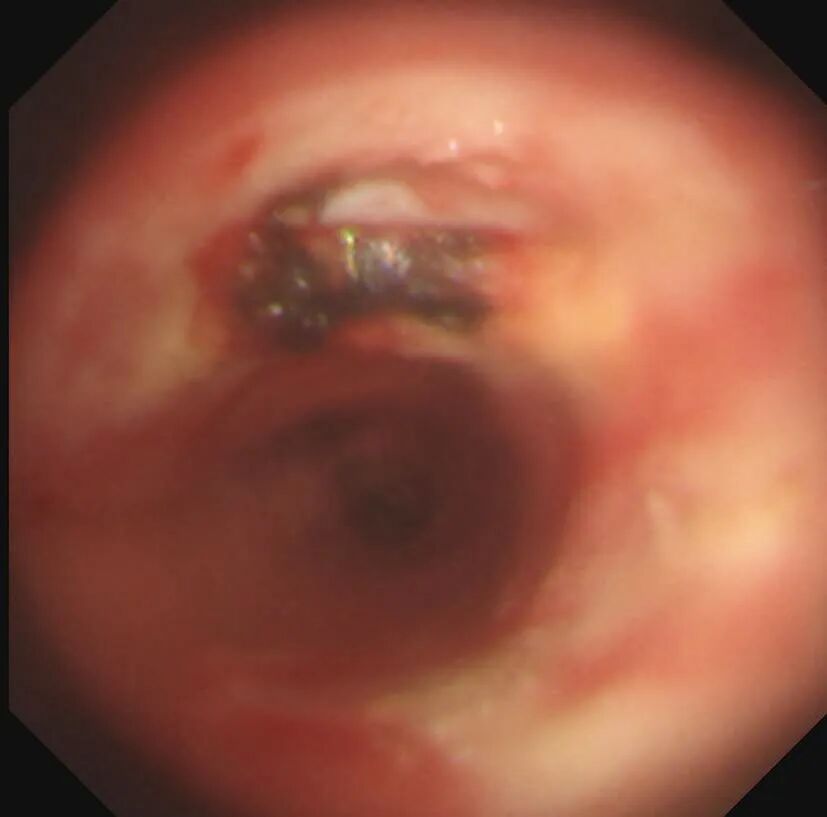

纖支鏡前

氣道介入手術空間狹窄,無疑增加了手術難度,圈套器在內鏡??谱o士協(xié)助下被劉和平主任送到了患者氣管內腫物附近,劉和平主任小心翼翼用圈套器、高頻電刀、氬氣刀及冷凍對腫物進行肢解分割、鉗夾取出、再肢解分割、再冷凍取出。